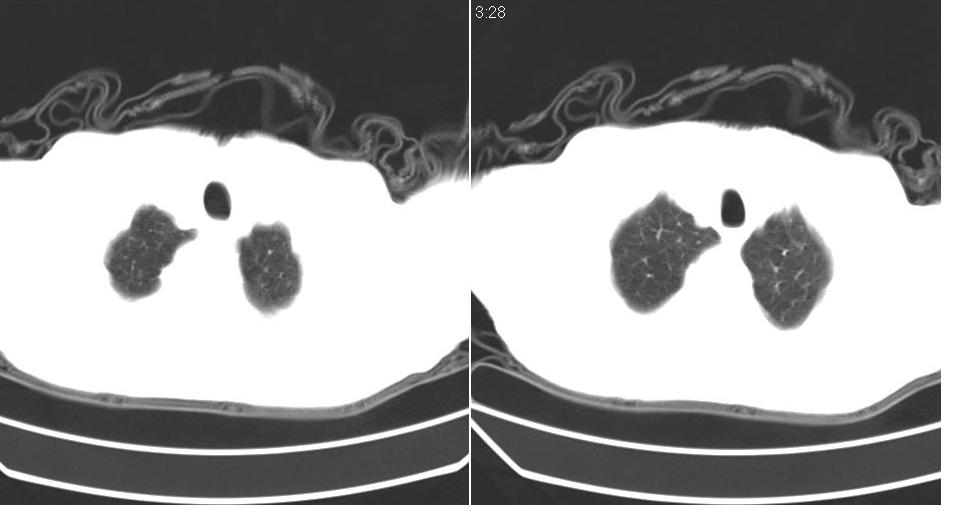

左肺下叶略萎陷、实变,内可见含气支气管征。左舌叶、中叶亦见少许斑片状高密度区,边界不清。纵隔未见肿大淋巴结影。

左下肺体积缩小,密度增高,见片增密影。边界模糊,见支气管充气像,肺门纵隔无异示,心脏气管左移,左侧胸腔少量积液。考虑肺部感染伴部分肺不张[有脑梗塞病史坠积性肺炎可能]

1、左肺下叶后基底段炎症并膨胀不全。

2、左侧胸腔积液。

左肺下叶体积缩小,成类楔形软组织影,其内可见部分含气支气管影,相应左侧肺门区未见明显肿块,考虑炎性病变,建议抗炎后短期复查